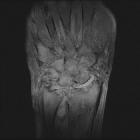

MRI

MRI is particularly sensitive to the early and subtle features of RA.

Commonly used sequences include T1-weighted contrast-enhanced spin-echo with fat saturation and T2-weighted spin-echo or gradient-echo sequences .

Features of RA best demonstrated with MRI include :

- synovial hyperemia: an indication of acute inflammation

- synovial hyperplasia (rice bodies)

- pannus formation

- decreased thickness of cartilage

- subchondral cysts and erosions:

- MRI is much more sensitive than radiography

- it is thought that subchondral cysts in RA eventually progress to erosions (i.e. constitute "pre-erosions")

- contrast enhancement may distinguish erosions or pre-erosions from degenerative subchondral cysts

- juxta-articular bone marrow edema

- joint effusions